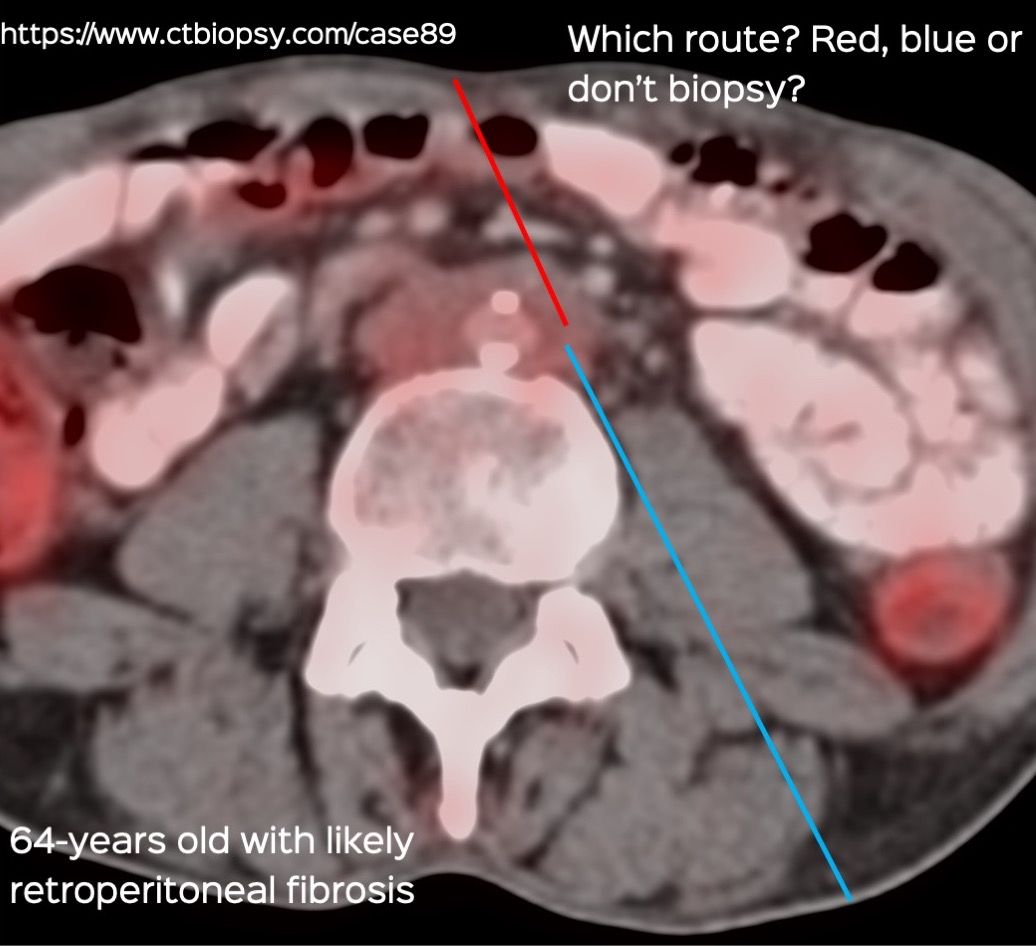

Case 89: Biopsy of Retroperitoneal Fibrosis

Biopsy of retroperitoneal fibrosis is possible under CT guidance

I decided to use a prone approach from the left.